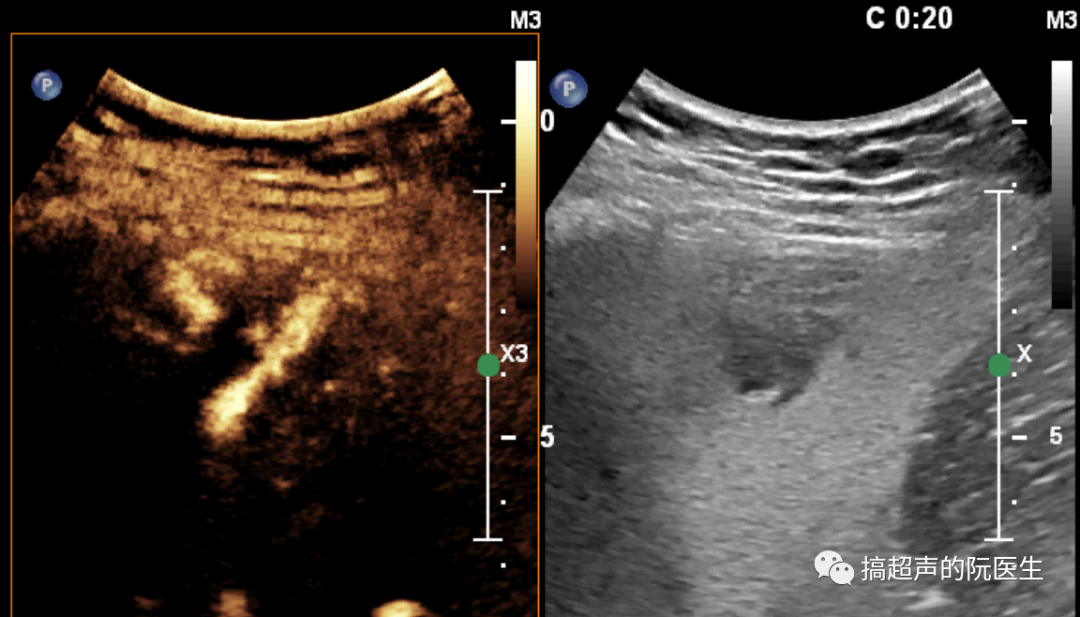

近日,在科室副主任趙華云副主任醫(yī)師的指導(dǎo)下,西安高新醫(yī)院超聲科成功為兩名肝臟局灶性結(jié)節(jié)性增生(FNH)患者及一名膽囊腺肌癥患者進(jìn)行了超聲造影檢查。此項(xiàng)檢查的順利開展,也意味著科室的診斷水平邁上了一個(gè)新的臺(tái)階。